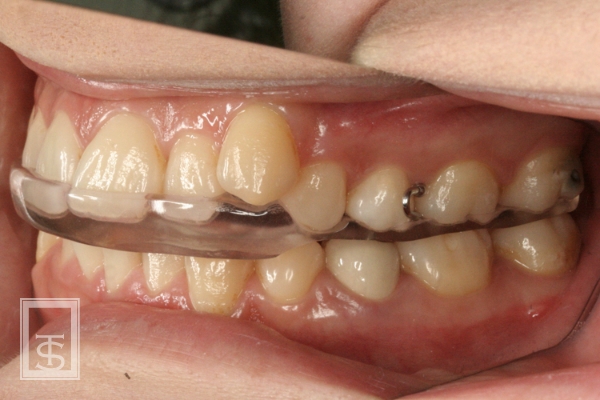

スプリント療法(Splint therapy)

顎関節症治療に用いられている方法で、マウスピース型の装置を口腔内にはめて、顎関節症の原因となっている口腔習癖や左右の顎のアンバランスを改善する治療法となります。

顎関節症状の有る場合、潜在的に顎関節のリスクが高い場合、顎位の不安定な場合などに症状の改善、顎関節のリスク評価、顎位の確認などに行います。

通常は上顎にマウスピース状の装置を使用します。

使用期間は症状や使用状況により異なります。